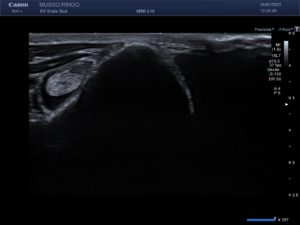

L’échographie musculo-tendineuse est particulièrement utile dans le diagnostic des tendinites aigues ou chroniques des tendons de l’épaule (notamment du biceps), mais aussi dans les diagnostics de contractures du muscle sous-épineux, de rupture de la corde du jarret, etc…

Cet examen peut être réalisé vigile ou sous sédation selon l’agitation et la douleur de l’animal et nécessite une tonte de la zone concernée et de la même zone du côté opposé au membre douloureux.